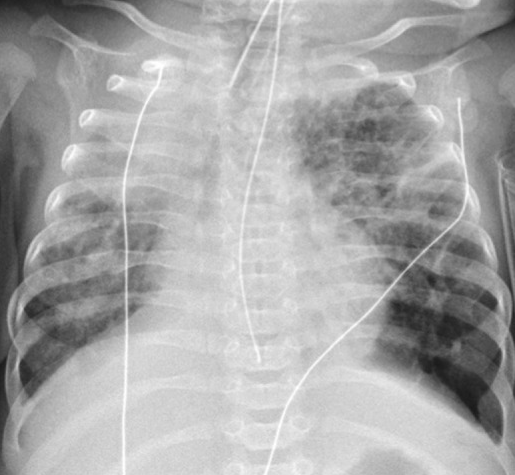

RX

- Zones d’hyperinflation et d’atélectasies

- Epaississement interstitiel (exsudat d’éosinophile)